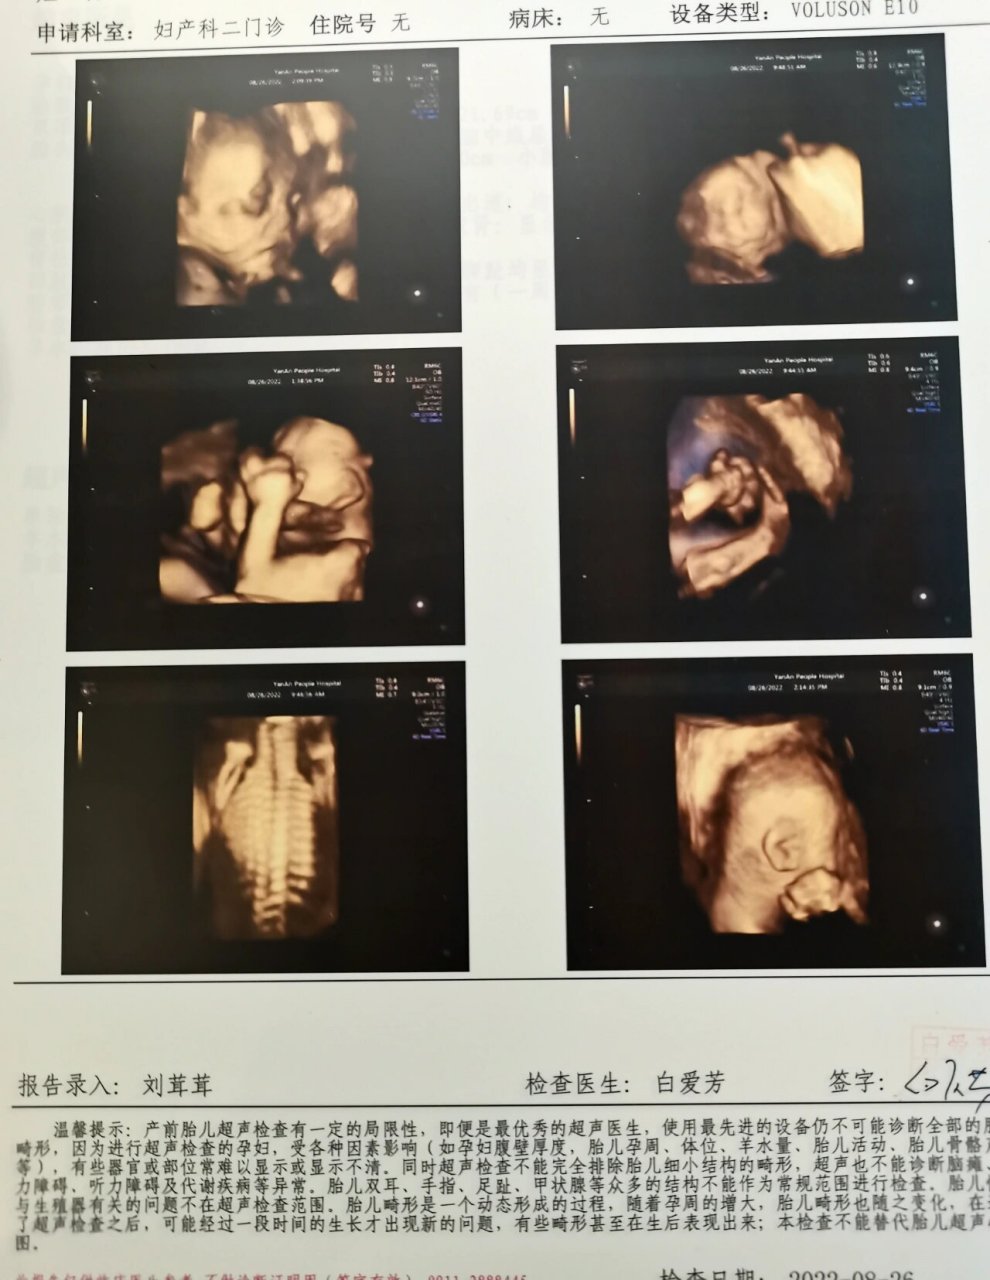

今天四维一次过 看到脸的一瞬间 在安静中忍不住笑出了声哈哈哈

"新鲜出炉的四维,你的第一张照片" 你忙着长大,我忙着长胖 - 抖音

宝贝你很乖四维一次通过73,爸爸妈妈也是第一次看到你清晰的脸庞,大

四维已过 二胎不查男女 健康就好

"新鲜出炉的四维,你的第一张照片"